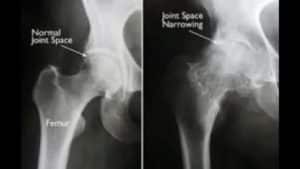

- اشعه ایکس (Radiography): در اشعه ایکس می توان فاصله مفصلی (Joint space) را اندازه گیری کرد. کاهش فاصله مفصلی می تواند نشان دهنده آرتروز مفصل لگن باشد.